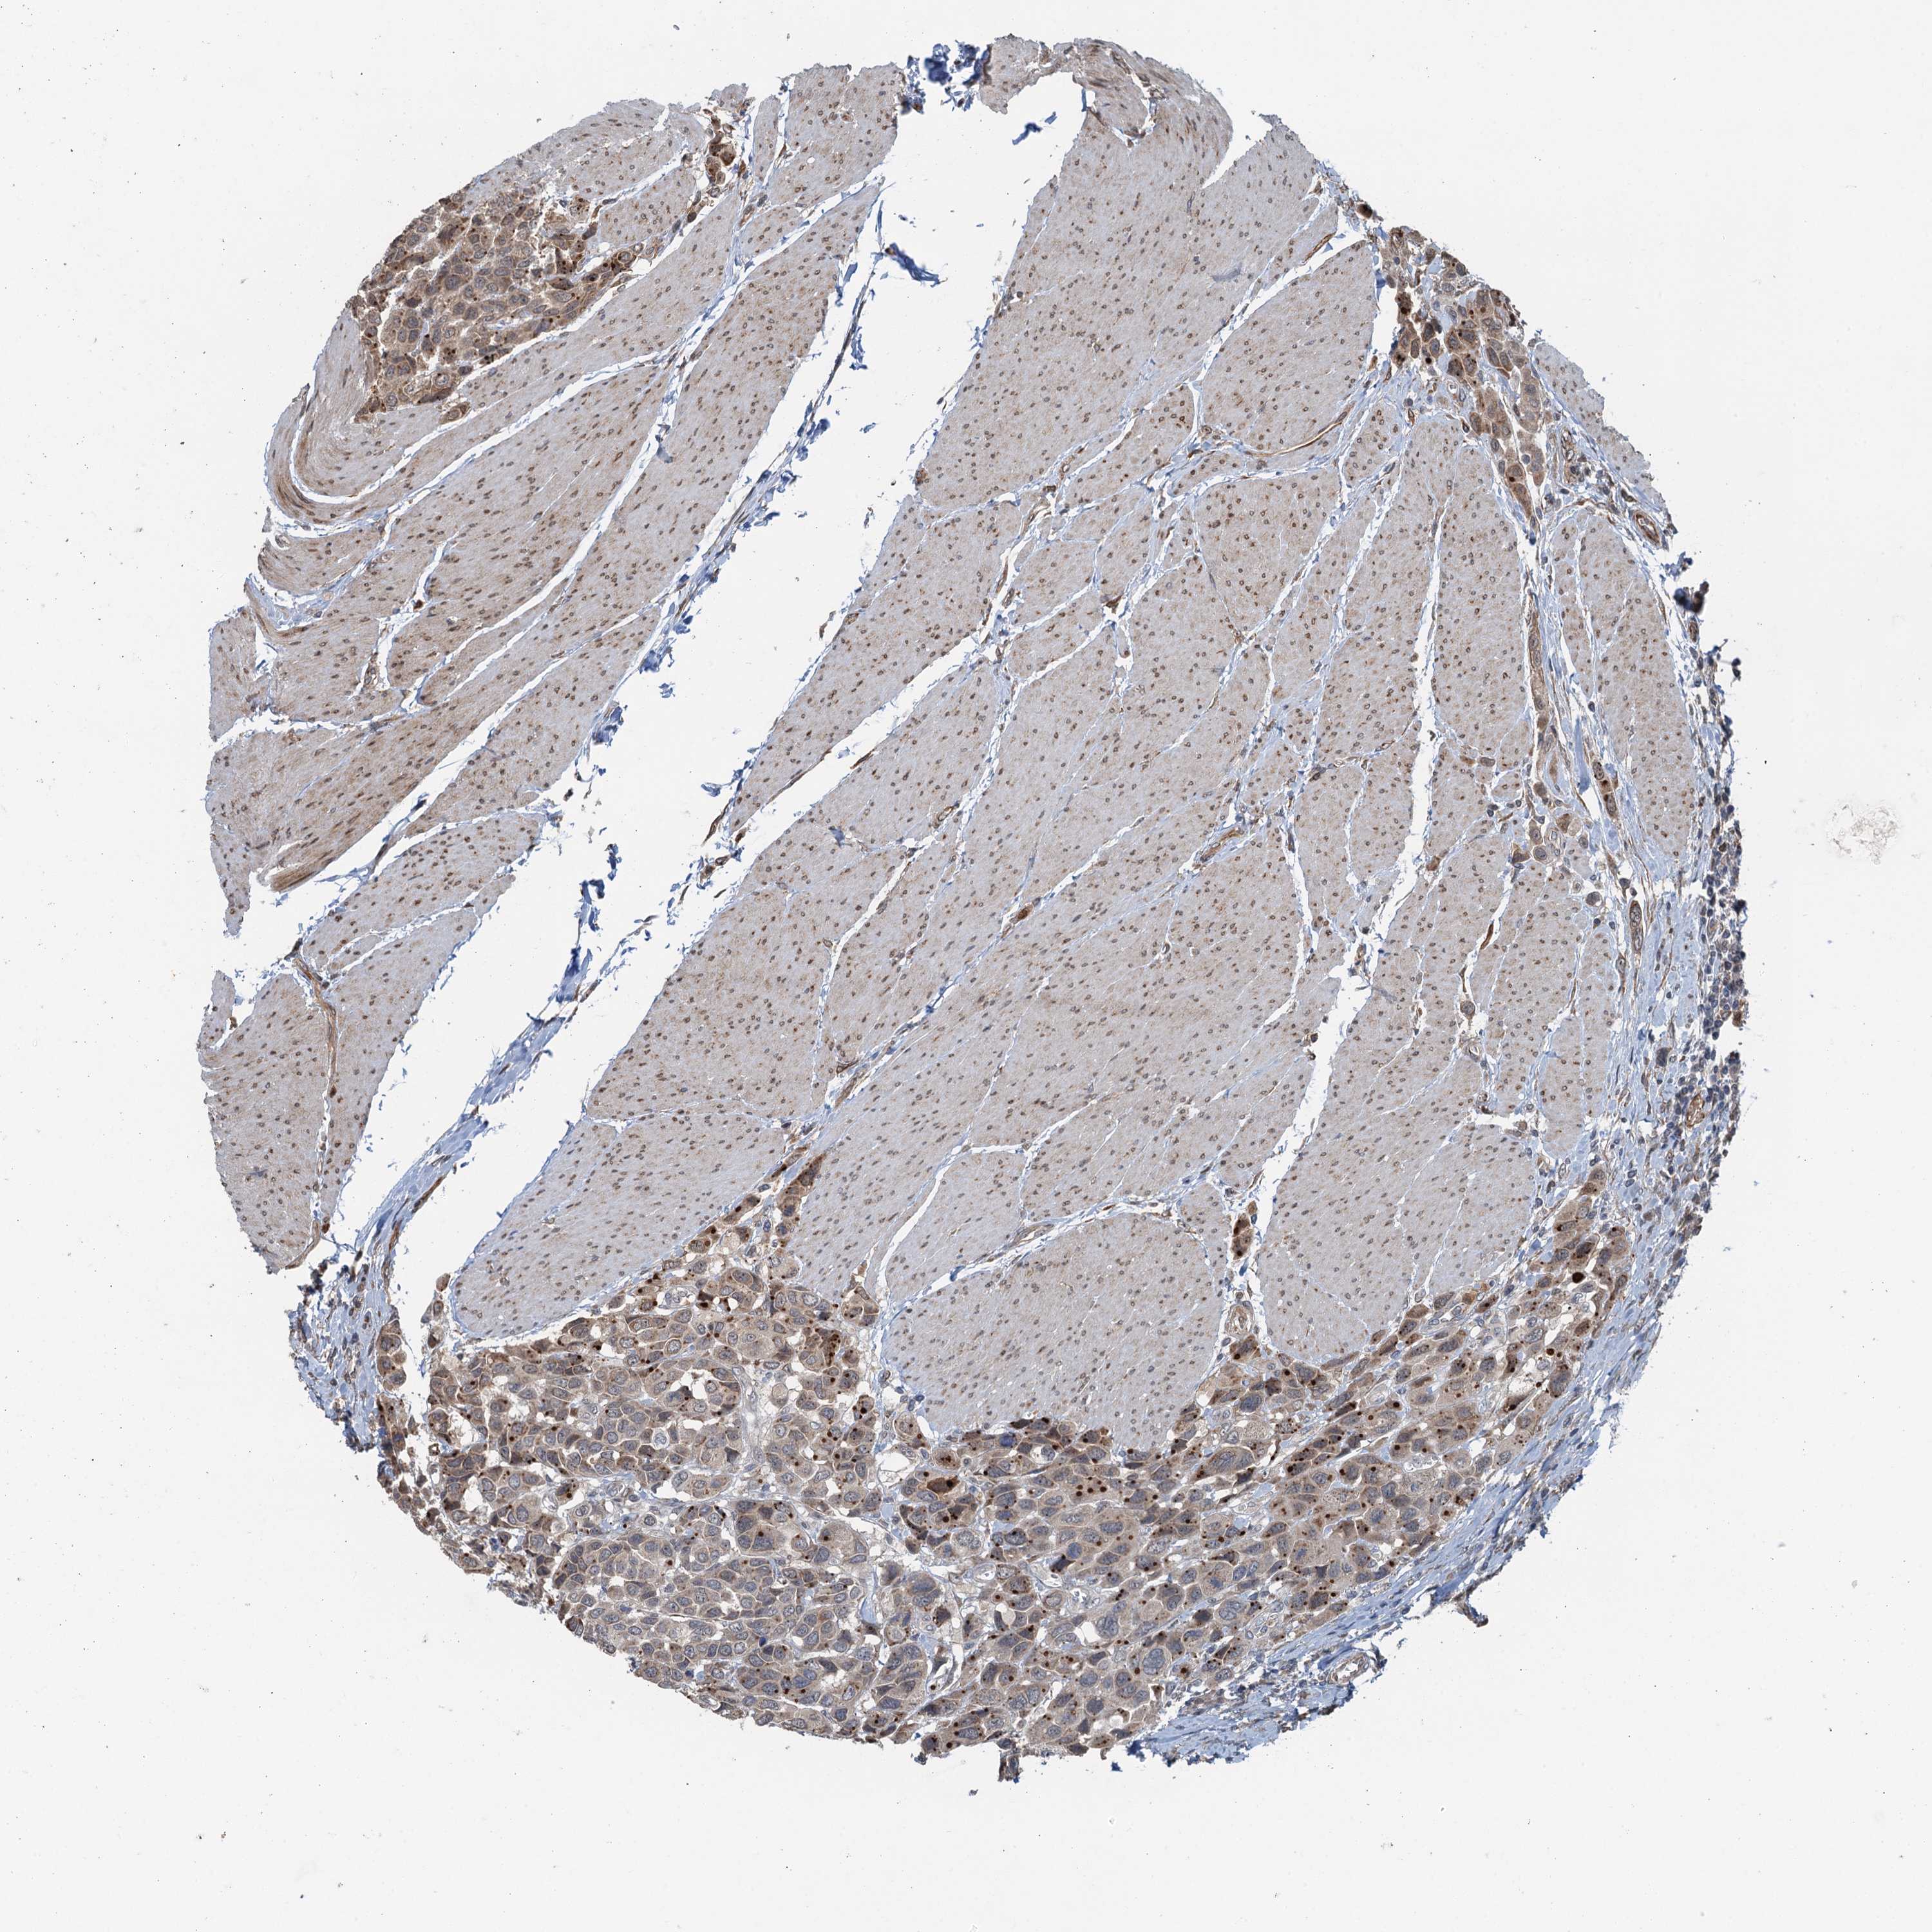

UROTHELIAL CANCER - Protein expressioni

A mouse-over function shows sample information and annotation data. Click on an image to view it in a full screen mode. Samples can be filtered based on level of antibody staining by selecting one or several of the following categories: high, medium, low and not detected. The assay and annotation is described here.

Note that samples used for immunohistochemistry by the Human Protein Atlas do not correspond to samples in the TCGA dataset.

Antibody stainingi

Antibody staining in the annotated cell types in the current human tissue is reported as not detected, low, medium, or high, based on conventional immunohistochemistry profiling in selected tissues. This score is based on the combination of the staining intensity and fraction of stained cells.

Each image is clickable and will lead to virtual microscopy that enables deeper exploration of all samples and also displays staining intensity scores, fraction scores and subcellular localization as well as patient and tissue information for each sample.

Antibody HPA039690

Antibody HPA040231

Staining

High

Medium

Low

Not detected

Intensity

Strong

Moderate

Weak

Negative

Quantity

>75%

75%-25%

<25%

None

Location

Nuclear

Cytoplasmic/membranous

Cytoplasmic/membranous,nuclear

Urothelial carcinoma, High grade

Urothelial carcinoma, Low grade